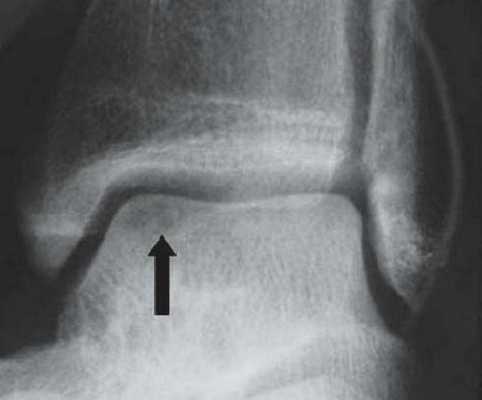

Не смотря на то, что Loomer с соавт. сообщили, что только от 50% до 66% остеохондральных дефектов обнаруживаются при помощи обычной рентгенографии, данный метод является важной отправной точкой и может быть полезен для исключения другой патологии голеностопного сустава [20]. Рентгенологическое исследование голеностопного сустава должно включать переднюю, заднюю и в 3⁄4 внутренней ротации проекции. Все проекции выполняются стоя (под нагрузкой) и называются функциональными. Функциональные рентгенограммы могут быть полезны для выявления сопутствующей нестабильности голеностопного сустава, проекция 3⁄4 во внутренней ротации, помогает в визуализации щели межберцового синдесмоза, а так же отображает передне-внутрений импижмент (таранной и большеберцовой кости) в случае его наличия. Выполненные в положении подошвенного сгибания прямая и 3⁄4 проекция во внутренней ротации могут быть полезны в выявлении заднемедиального поражения таранной кости. Рентгенологические признаки, которые могут быть определены, варьируются от небольших участков сдавления субхондральной кости до крупных отслоенных остеохондральных фрагментов. Радиографическая

система классификации была разработана Berndt и Harty в 1959 году и остается золотым стандартом. (Табл. 1) [16]. Loomer с соавторами дополнили имеющуюся классификацию, на основе не только рентгенограмм, а также МРТ (магнитно-резонансная томография) и КТ (компьютерная томография), и добавили стадию V в систему классификации Berndt и Harty [22].

На КТ определяется остеохондральное повреждение таранной кости.

Рентгенография

Рутинное рентгенологическое исследование включает рентгенографию обоих голеностопных суставов в прямой и боковой проекциях. На рентгенограммах можно увидеть отслоенный костный фрагмент. Изначально, на начальных стадиях болезни, площадь повреждения может быть очень мала, в связи с чем она не будет видна на рентгенограммах. Иногда изменения становятся видны только при рентгенологическом исследовании в динамике.